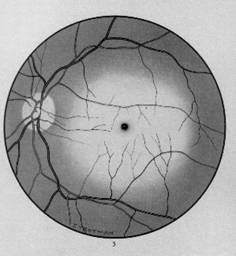

exsudate dure reprezentand expresia organizarii edemului retinian, sub forma de pete alb-galbui, stralucitoare, bine delimitate, in general determinate de lipidele extravazate prin peretele vascular; la nivelul regiunii maculare sunt dispuse intre fibrele nervului optic, dand aspectul de stea maculara (Fig. 17.3).

Fig. 17.3 - Retinopatie hipertensiva